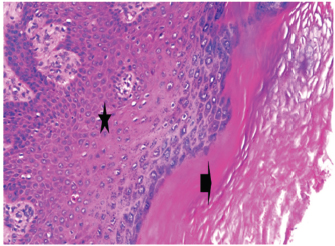

At 7 days post wounding; the inflammatory reaction was moderate and characterized by polymorphonuclear cells and macrophages infiltration with the presence of small scab covering the wound surface. Early evidence of epithelization was detected and represented by the proliferation of epidermal epithelium under the scab. There was marked thickening and hyperplastic proliferation of epidermal epithelium at the free wound edge (Fig. 6). The dermal tissue underlying the wound area showed few polymorphonuclear cells infiltration and more abundant mononuclear cells. Fibroplasia and angiogenesis were detected in the dermis and more extensive in deeper areas of the dermis which characterized by fibroblast and angioblast proliferation forming immature young granulation tissue (Fig. 7). At 14 days post wounding, the wound area was covered by a complete layer of epidermal epithelium indicating a good epithelization rate of the wound. Proliferation of cutaneous appendages was detected. The newly formed epithelium was thick and showed partial keratinization and epithelial differentiated stratum containing polyhedral keratinocyte with the appearance of keratohyalin granules in their cytoplasm (Fig. 8). The dermal tissue showed deposition of parallel well organized and interconnected collagen bundles that arranged parallel to epidermis associated with enhanced angiogenesis represented by well-developed blood capillaries (Fig. 9). At 21 days post wounding, remodeling of the formed epithelium with relatively small scar formation and mild restoration of skin appendages. Keratinized and differentiated stratum comprising the covering epithelium and the newly formed skin appendages from the basal epidermal epithelium were detected (Fig. 10). The dermal tissue revealed well-formed organized tissue consisted of parallel compact and interconnected bundles of collagen with scant angiogenesis (Fig. 11). At 28 days post wounding, well-formed scar tissue covering highly cellular organized tissue was detected (Fig. 12). The dermal tissue revealed well-arranged compact collagen bundles containing scarce blood vessels (Fig. 13).

Fig. 6. Skin of a goat from electroacupuncture group at 7 days post wounding showing early evidence of epithelization, hyperplastic proliferation of epidermal epithelium (arrow head) at the free wound edge, and moderate inflammatory cells infiltrations in the dermis (arrow), (HE ×100).

Fig. 7. Skin of a goat from electroacupuncture group at 7 days post wounding showing fibrin exudation at wound surface with dermal edema, hemorrhages (arrow) with moderate mononuclear cells infiltration associated with formation of immature granulation tissue consisted of fibroblast and angioblast forming small blood channels (arrow head), (HE ×200).